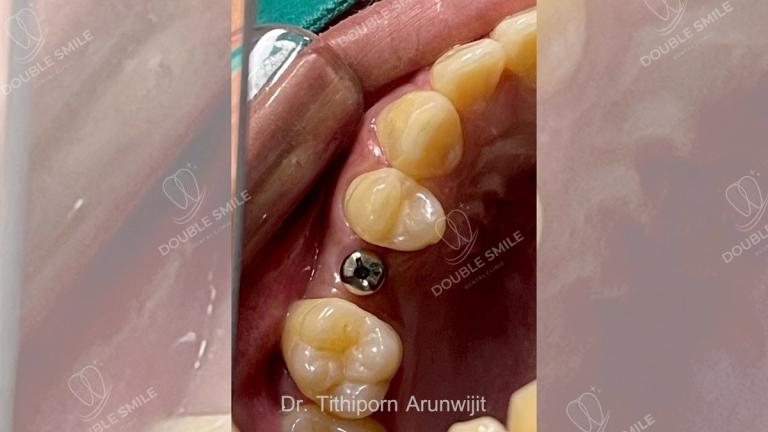

เคสรีวิวรากเทียม 17

Case Review

Before & After